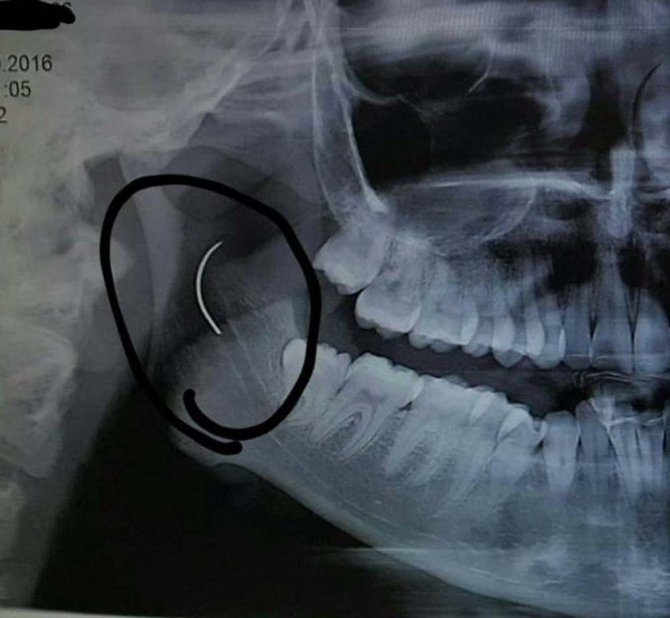

Soma Devlet Hastanesi'nde bademcik şikayetiyle 1999 yılında ameliyat olan Meltem Cansız'ın boğazında iğne unutuldu. 18 yıl boyunca boğazında iğne ile yaşayan ve şu anda 21 yaşında olan Meltem Cansız'ın tüm hayatı acı ve ağrılarla geçti. Boğazındaki iğnenin acıları günden güne yıldan yıla artan Meltem Cansız, 11 yıl sonra 14 yaşında iğnenin fark edilmesiyle Ege Üniversitesi'nde bıçak altına yattı ancak ameliyatı başarısız geçti. Lise öğreniminden sonra sağlık sorunları nedeniyle üniversiteye hazırlanamayan Meltem Cansız, acılarına rağmen yılmadı sabırla bekledi ve geçirdiği başarılı ameliyatla o iğneden 18 yıl sonra kurtuldu.

Boğazındaki iğneyle geçen 18 yılını anlatan Meltem Cansız, "3 yaşında geçirdiğim bademcik ameliyatında iğne boğazımda unutulmuş. Daha sonra iğneden dolayı 11 yıl sonra 14 yaşındayken kulak rahatsızlığım ortaya çıktı. Kafamın sağ tarafı ağrımaya başladı. Doktora gittik, hiçbir şey olmadığını söylediler. Sonrasında beni MR çekilmek üzere Akhisar'a yönlendirdi. Gecenin bir vakti MR'a girdim. Ancak bir türlü çekemediler. Benim üzerimde toka vs. metal bir şey olduğunu söylediler baktılar ancak bir şey yoktu. Üç yada dört defa MR'a girdim. Ancak bir türlü çekemediler. Sonra doktorumuz röntgene yönlendirdi. Röntgen görüntüsünde ameliyattan kalma bir çengelli iğnenin boğazımda olduğu görüldü. Bunun için beni Ege Üniversitesi'ne sevk ettiler. Burada doktorlar bu ameliyatı yapabileceklerini ancak riskinin çok olduğunu söylediler. Biz yine de kabul ettik. 1,5 saatlik operasyon geçirdim ancak iğneyi bulmadıklarını söylediler. 2 sene kadar araştırma yaptık. Birçok hastaneyle görüştük. Ancak ayağımda bir rahatsızlık meydana geldi. Ayağım için Ege Üniversitesi'ne gittik. Tekrardan beni ameliyat eden doktorumla görüştüm. "Seni ben ameliyat ettim, tekrardan buna kalkışamam" dedi. MR'a da giremezsin dediler. "Sen bununla yaşamayı öğren" en azından bunun için çabalama alınmaması daha iyi dediler. Ben daha genç bir kızım sonuçla bu iğneyle ömür boyu yaşayamazdım. Yaşanan bu olumsuzların ardından araştırmalarımız neticesinde en son İzmir'de özel bir hastaneye gittik. Oradaki doktorum Çağlar Çallı bey bana umut verdi. "Bu iğneyi alacağız" dedi. İnancımı kaybetmedim, sonucun ne olacağını bilmeden girdim ben o ameliyata. Ölüm, felç olma riskim çok fazlaydı. "Yaşayamayabilirsin" dediler, biz bile bile lades dedik. Sonucu da güzel oldu" dedi.

Baba Ahmet Cansız ise kızını 1999 yılında 3 yaşındayken bademcik sorunu nedeniyle Soma Devlet Hastanesi'ne götürdüğünü belirterek, "Bademcikleri nedeniyle çok sık hasta oluyordu. O günkü SSK'da doktorumuz ameliyat olması gerektiğini söyledi. Neticede ameliyat olduk. Ameliyat sonrasında aradan geçen süreçte kızım 17 yaşında geldiğinde yüzünde, sağ tarafında bir ağrının olduğunu, başının, kulağının ağrıdığını söyleyince kulak burun boğaz doktoruna gittik. İlaçlar verdi geçmedi, sonra bir daha gittik. Eklem arası bir iltihap olabilir diyerek MR istedi. Akhisar ilçesine MR çekilmeye gittik. Fakat bir türlü çekemediler. Daha sonra bir film çekildi ve iğne ortaya çıktı" diye konuştu.

Ege Üniversitesi'ne gittiklerini belirten baba Cansız, iğnenin şah damarına çok yakın olduğunun söylendiğini belirterek şunları söyledi:

"Doktorlar çok tehlikeli bir ameliyat olacağını yanlış ya da en ufak bir hatada kızımızın bir tarafının felç kalabileceğini veya hayatını kaybedebileceğini söylediler. Biz bu riski göze alarak ameliyata müsaade ettik. Fakat iğneyi görüldüğü yerde bulamadıklarını söyleyerek alamadılar. Sonra İzmir Çiğli'de özel bir hastanede denedik. Kendisine binlerce kez teşekkür. Allah razı olsun. Çocuğumun boğazındaki iğneyi aldı. Dünyalar bizim oldu."